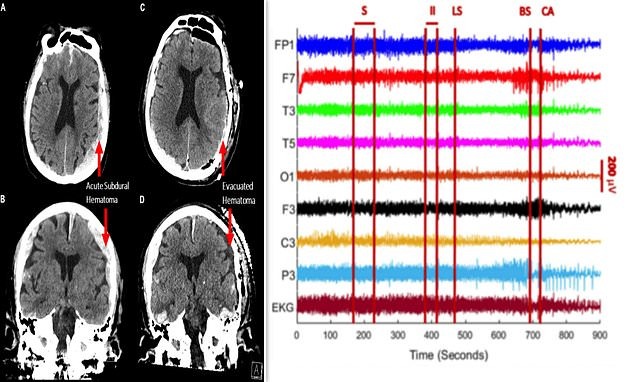

رجل ثمانيني تعرّض لأزمة صحية، تم إخضاعه لجهاز التخطيط الكهربائي للدماغ، ورصد سلوكه الدماغي لحظة بلحظة طيلة 15 دقيقة صعبة من الاحتضار

ففي التجربة، تمّ ملاحظة زيادة كبيرة في موجات "غاما" والتي ترتبط بعمليات مثل الأحلام والتّامل واستعادة الذّاكرة